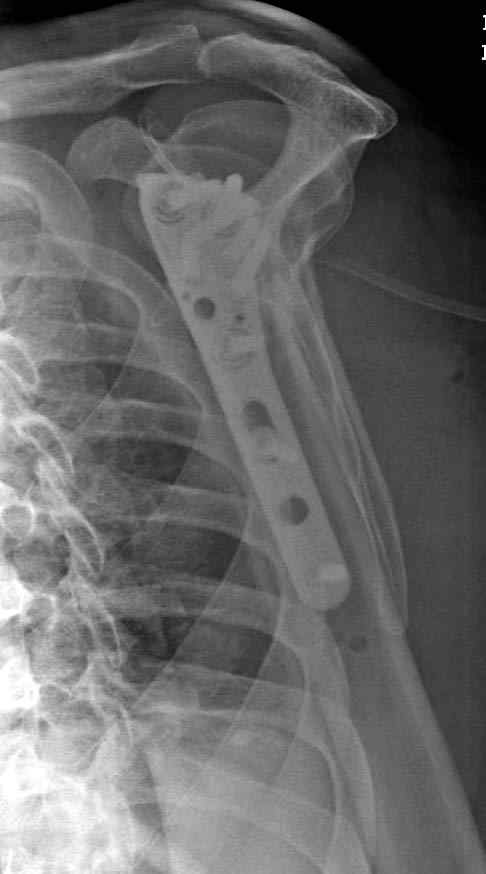

дополнительные снимки по протезированию